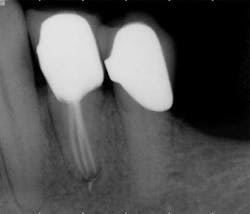

While mandibular incisors are my least favorite teeth to treat, the premolar teeth also provide significant reason for concern as they have highly variable anatomy. The maxillary first and second premolars will have one, two, or three roots and canals. (Figure 3) Maxillary premolar teeth have the smallest mean apical dimension at the apex (11) and the most variable anatomy, with exception of third molars. (12,17) The roots are often very thin, and a bulbous clinical crown may have significant taper to a thin root in the mesial-distal dimension that is broad in the facial-lingual dimension. It is not uncommon to see mesial-distal fractures in maxillary first or second premolars. Maxillary second premolars may have more curvature in the apical portion of the root when the sinus is close to the root ends. (Figure 4)

following root canal treatment in teeth Nos. 4 and 5. An angled

radiograph indicated a high probability for an untreated canal in

tooth No. 4 and as a result, this tooth was retreated.